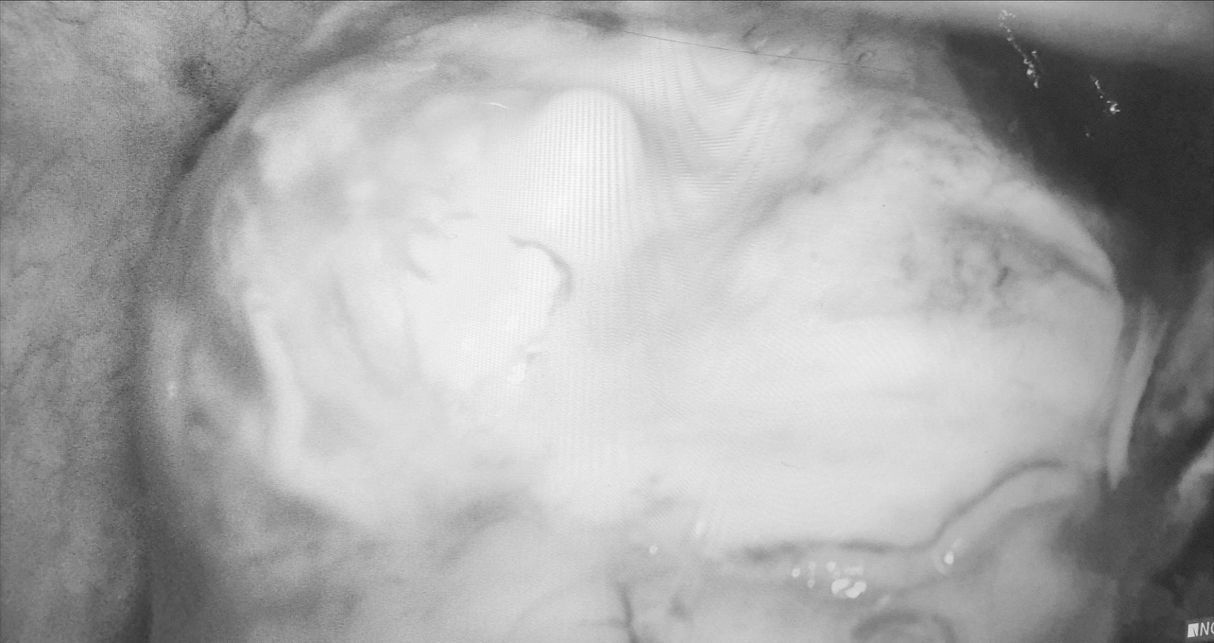

图为患者纵隔巨大脓肿及周围粘连(已黑白处理)